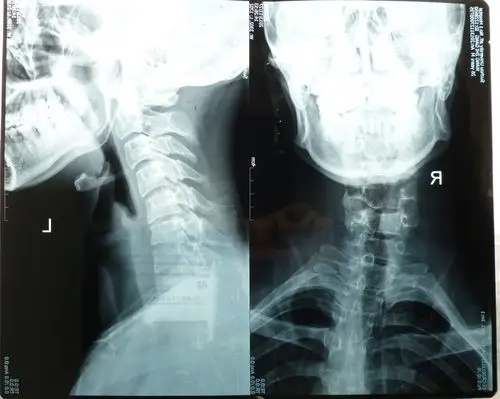

术后颈椎侧弯完全纠正该图片可能引起不适继续查看术后颈椎后凸畸形

正常颈椎

颈椎测弯 颈椎间盘突出 28岁(定期更新治疗进展,欢迎讨论)